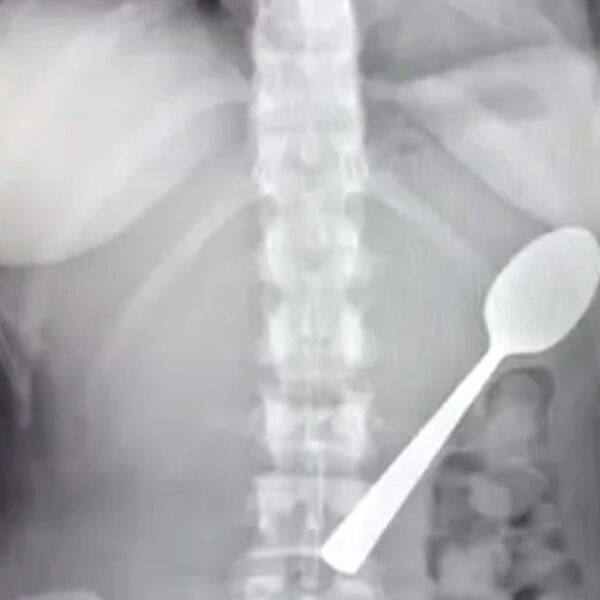

В Бельгии девушка случайно проглотила к 17-сантиметровую ложку из-за внезапного испуга, пишет What's The Jam.

Необычный случай произошел с 28-летней Рейми Амелинкс из Румста. Ее энергичная собака породы венгерская выжла по кличке Марли внезапно запрыгнула на колени, заставив Рейми резко дернуться. Девушка зажала ложку зубами, так как печатала двумя руками сообщение, поэтому предмет застрял в горле.

Рейми, работающая медицинским представителем, попыталась вытащить ложку рукой, но безуспешно. Когда ее бойфренд вернулся с работы, ей было так стыдно, что она промолчала и притворилась, будто ничего не произошло.

Только после ужина Рейми почувствовала, как ложка двигается внутри, вызывая вздутие, тошноту и прочие странные ощущения. Спать было невозможно в любом положении, и тогда она обратилась в больницу.

Врачи предупредили, что такая большая ложка не выйдет естественным путем, и назначили гастроскопию через два дня. Под местной анестезией ее повернули в желудке и удалили.

Рейми быстро пошла на поправку и сохранила ложку как сувенир, теперь ее возлюбленный хочет сделать из ложки «произведение искусства».